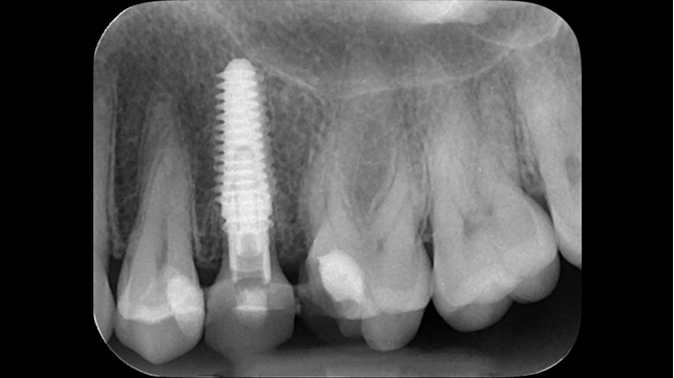

Clinical case: Extraction, immediate implant placement, & provisionalization

- Courtesy of Dr. Iulian Filipov, Romania -

AnyRidge, R2GATE, guided surgery, immediate placement, immediate provisionalization, initial stability, Dr. Iulian Filipov, #25, maxillary posterior, immediate loading, Mega ISQ

Products:

AnyRidge implant system, R2GATE, MEGA ISQ, Digital prosthesis